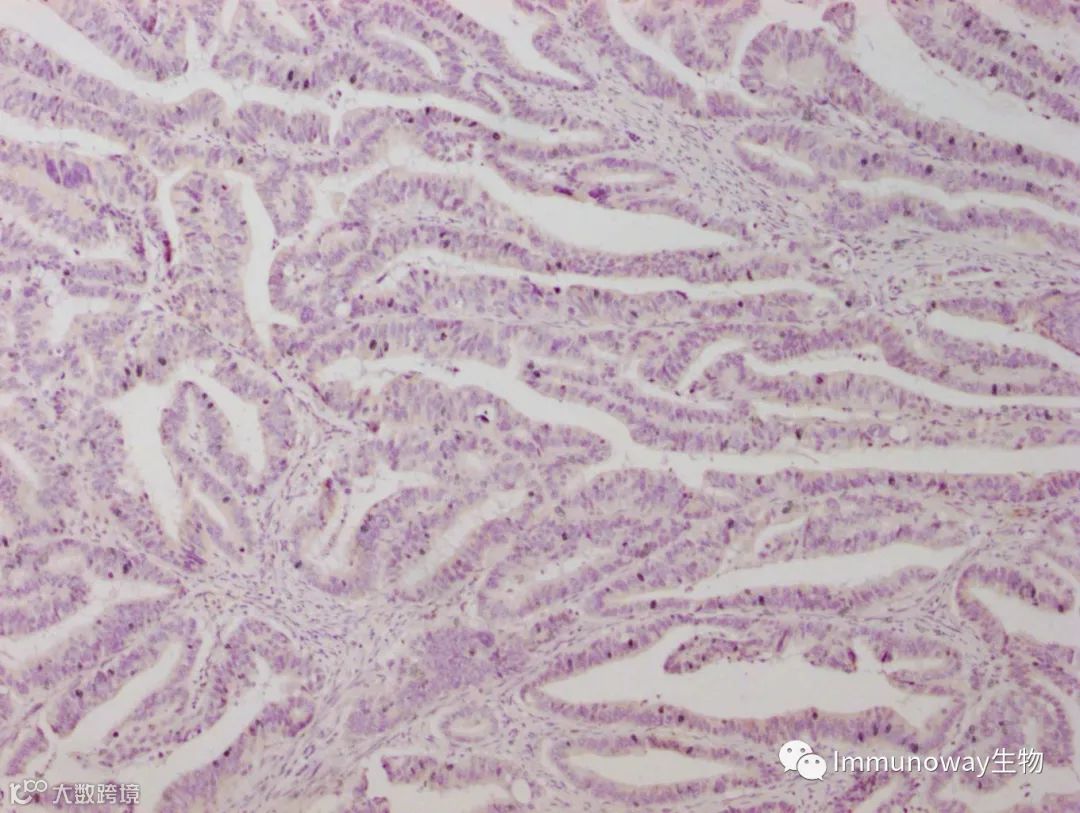

检测组织:结肠癌组织石蜡切片

二抗:普通直接酶标记二抗

结论:结果显色癌细胞胞浆胞膜弱阳性,低背景

二抗:病理级Polymer酶标记二抗

结论:结果显色癌细胞胞浆胞膜强阳性,低背景